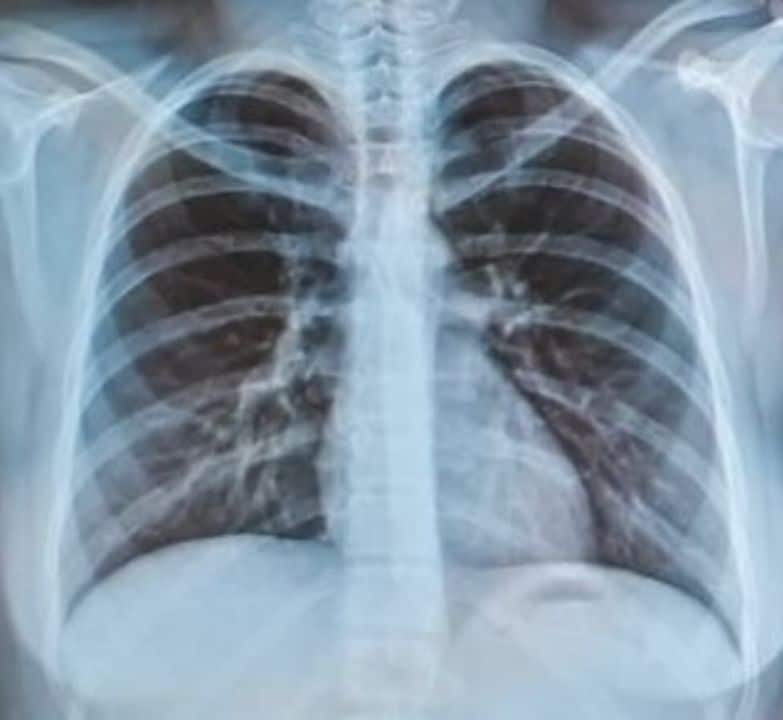

The doctor also described another patient affected by PM2.5 and air pollution who had an abnormal protein condition in the lungs.

The patient had previously required lung washing once or twice a year for the past five to six years, but had not progressed to respiratory failure requiring intubation.

However, less than two months after a previous lung wash, the patient returned with respiratory failure and needed a breathing tube. The doctor said the fluid collected during treatment was blood-stained, indicating much more severe inflammation than in earlier episodes.

He added that outside the haze season, the patient could usually wait several months between treatments without developing respiratory failure.

In this latest case, although protein sediment was lower than usual, widespread bleeding and increased bronchial mucus pointed to more severe lung injury and inflammation.